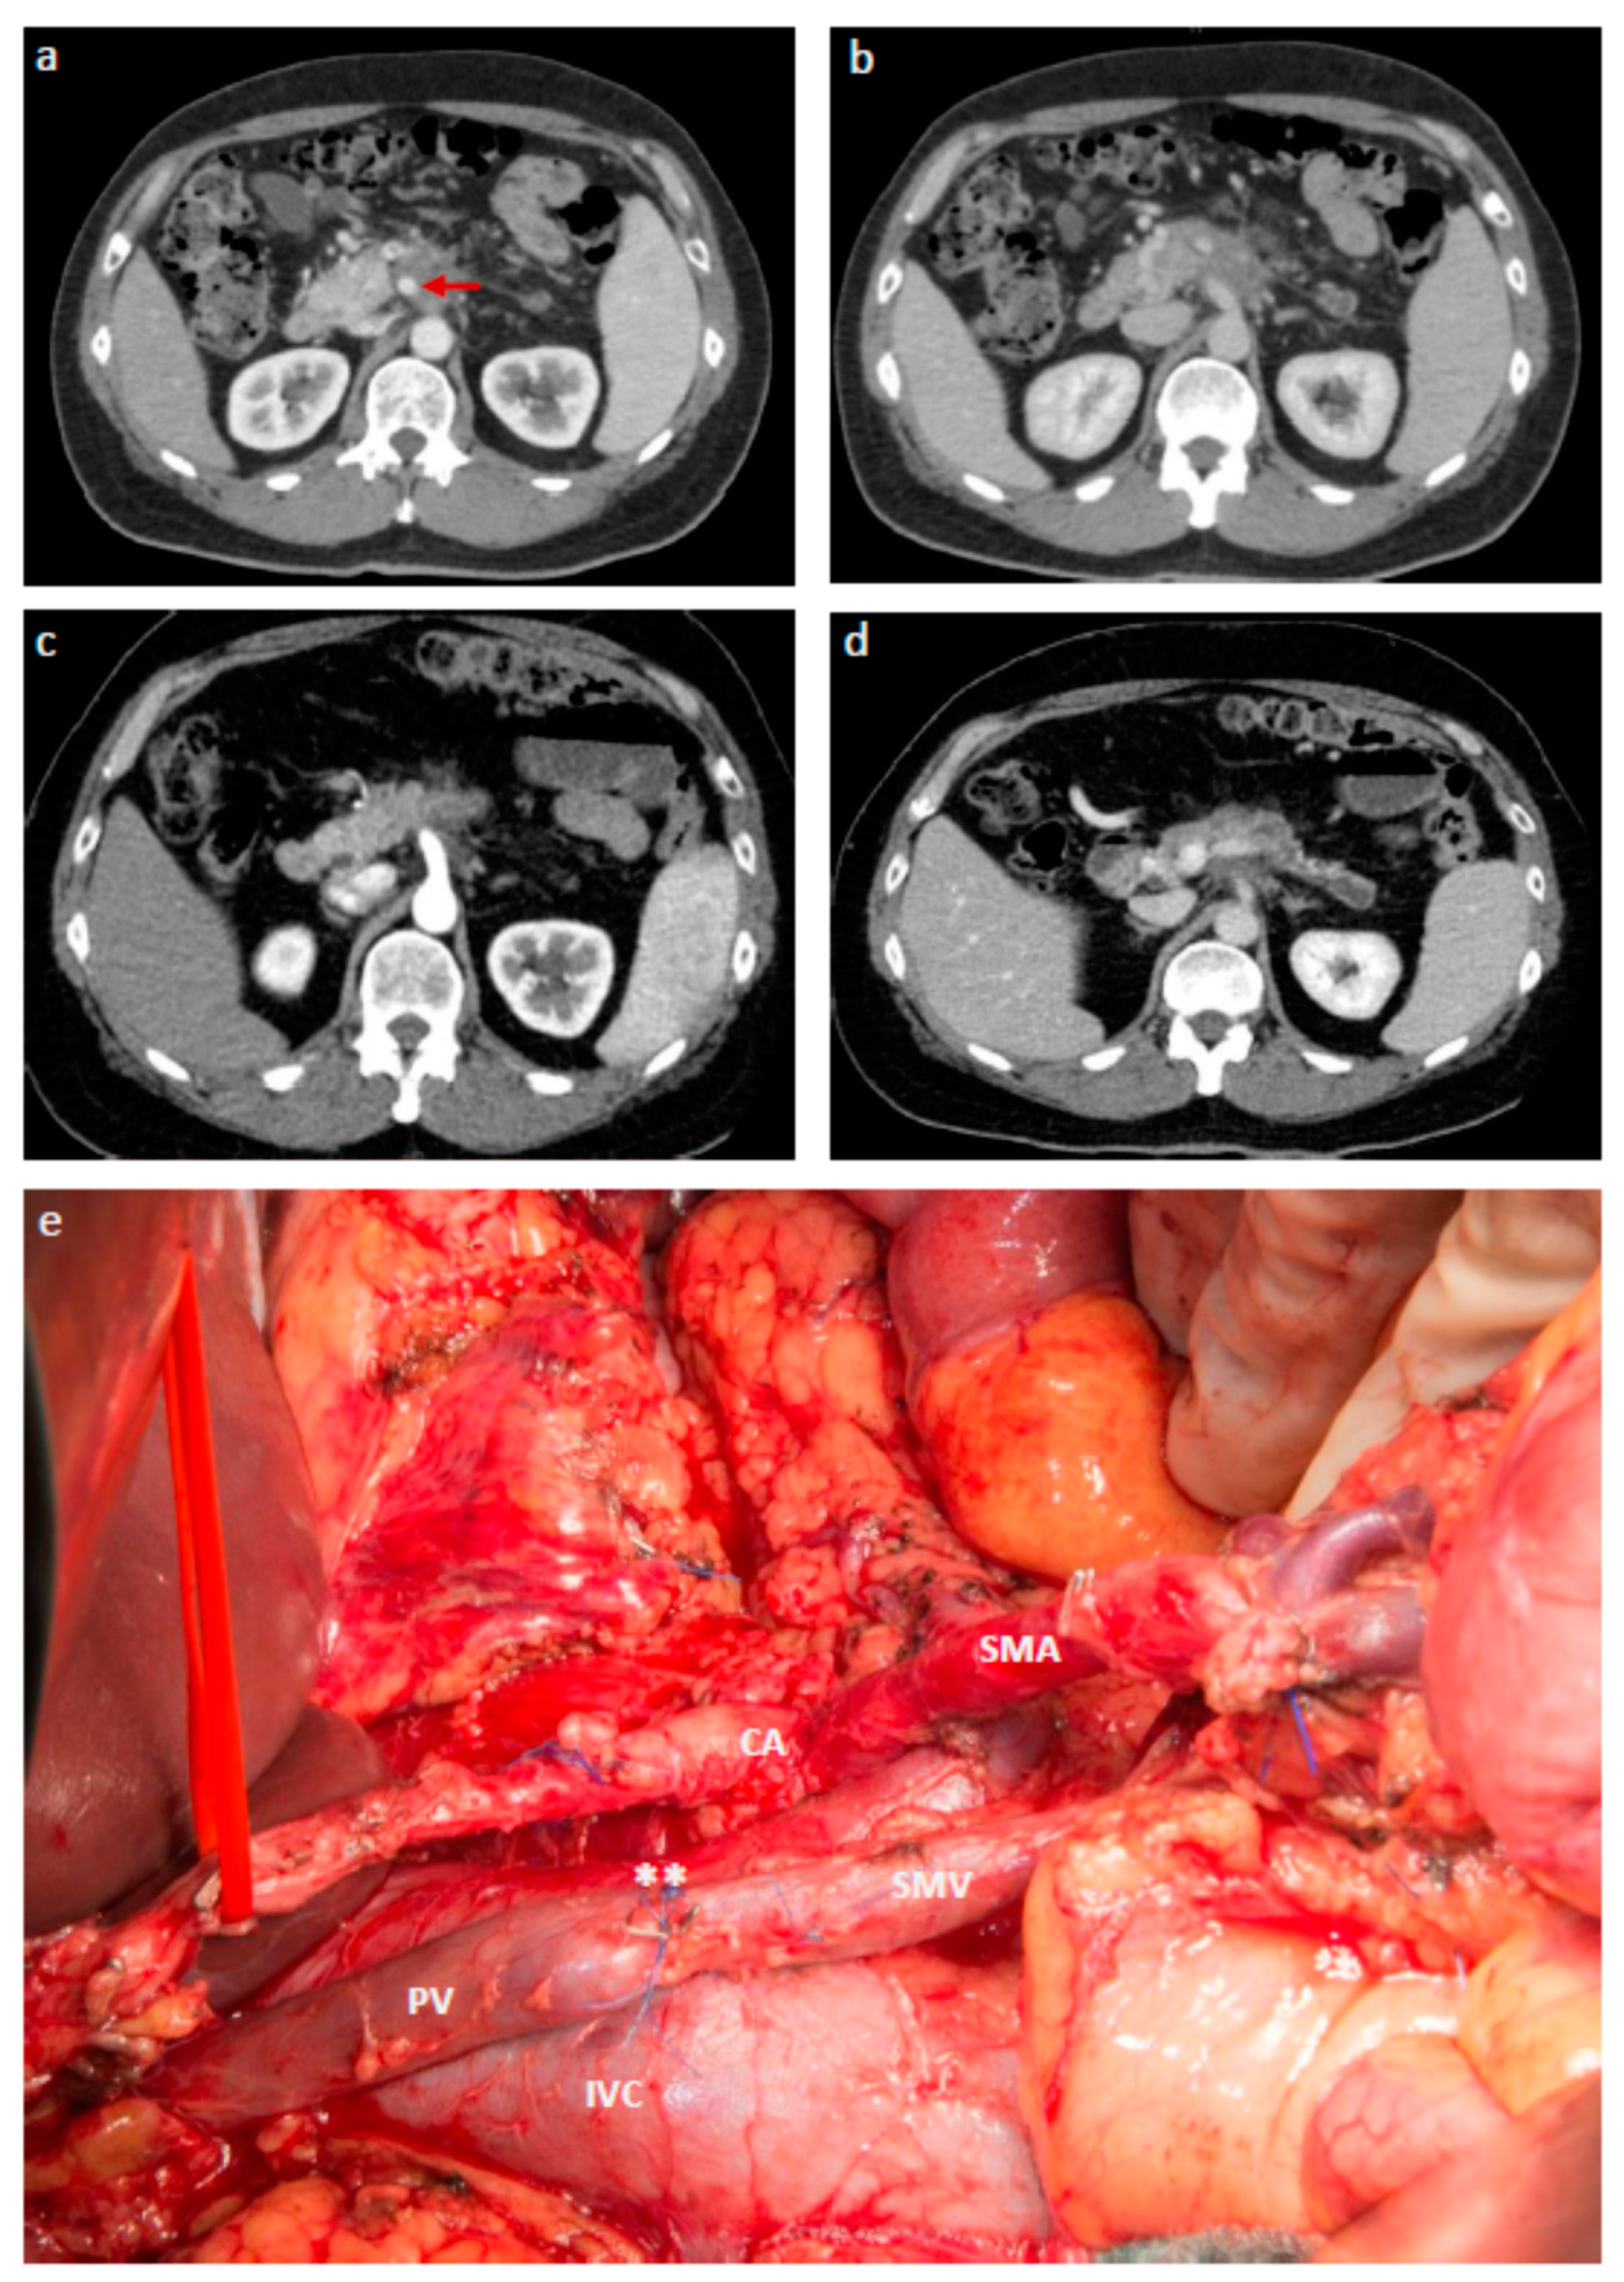

- Hackert, T.; Strobel, O.; Michalski, C.W.; Mihaljevic, A.L.; Mehrabi, A.; Muller-Stich, B.; Berchtold, C.; Ulrich, A.; Buchler, M.W. The triangle operation-radical surgery after neoadjuvant treatment for advanced pancreatic cancer: A single arm observational study. HPB 2017, 19, 1001–1007. [Google Scholar] [CrossRef] [PubMed]